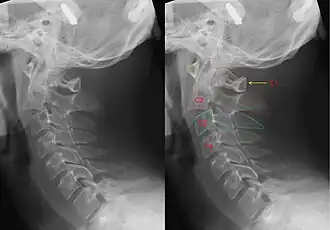

X-ray of the cervical spine with a Hangman's fracture. Left without, right with annotation. It can be seen clearly that C2 (red outline) is moved forward with respect to C3 (blue outline).